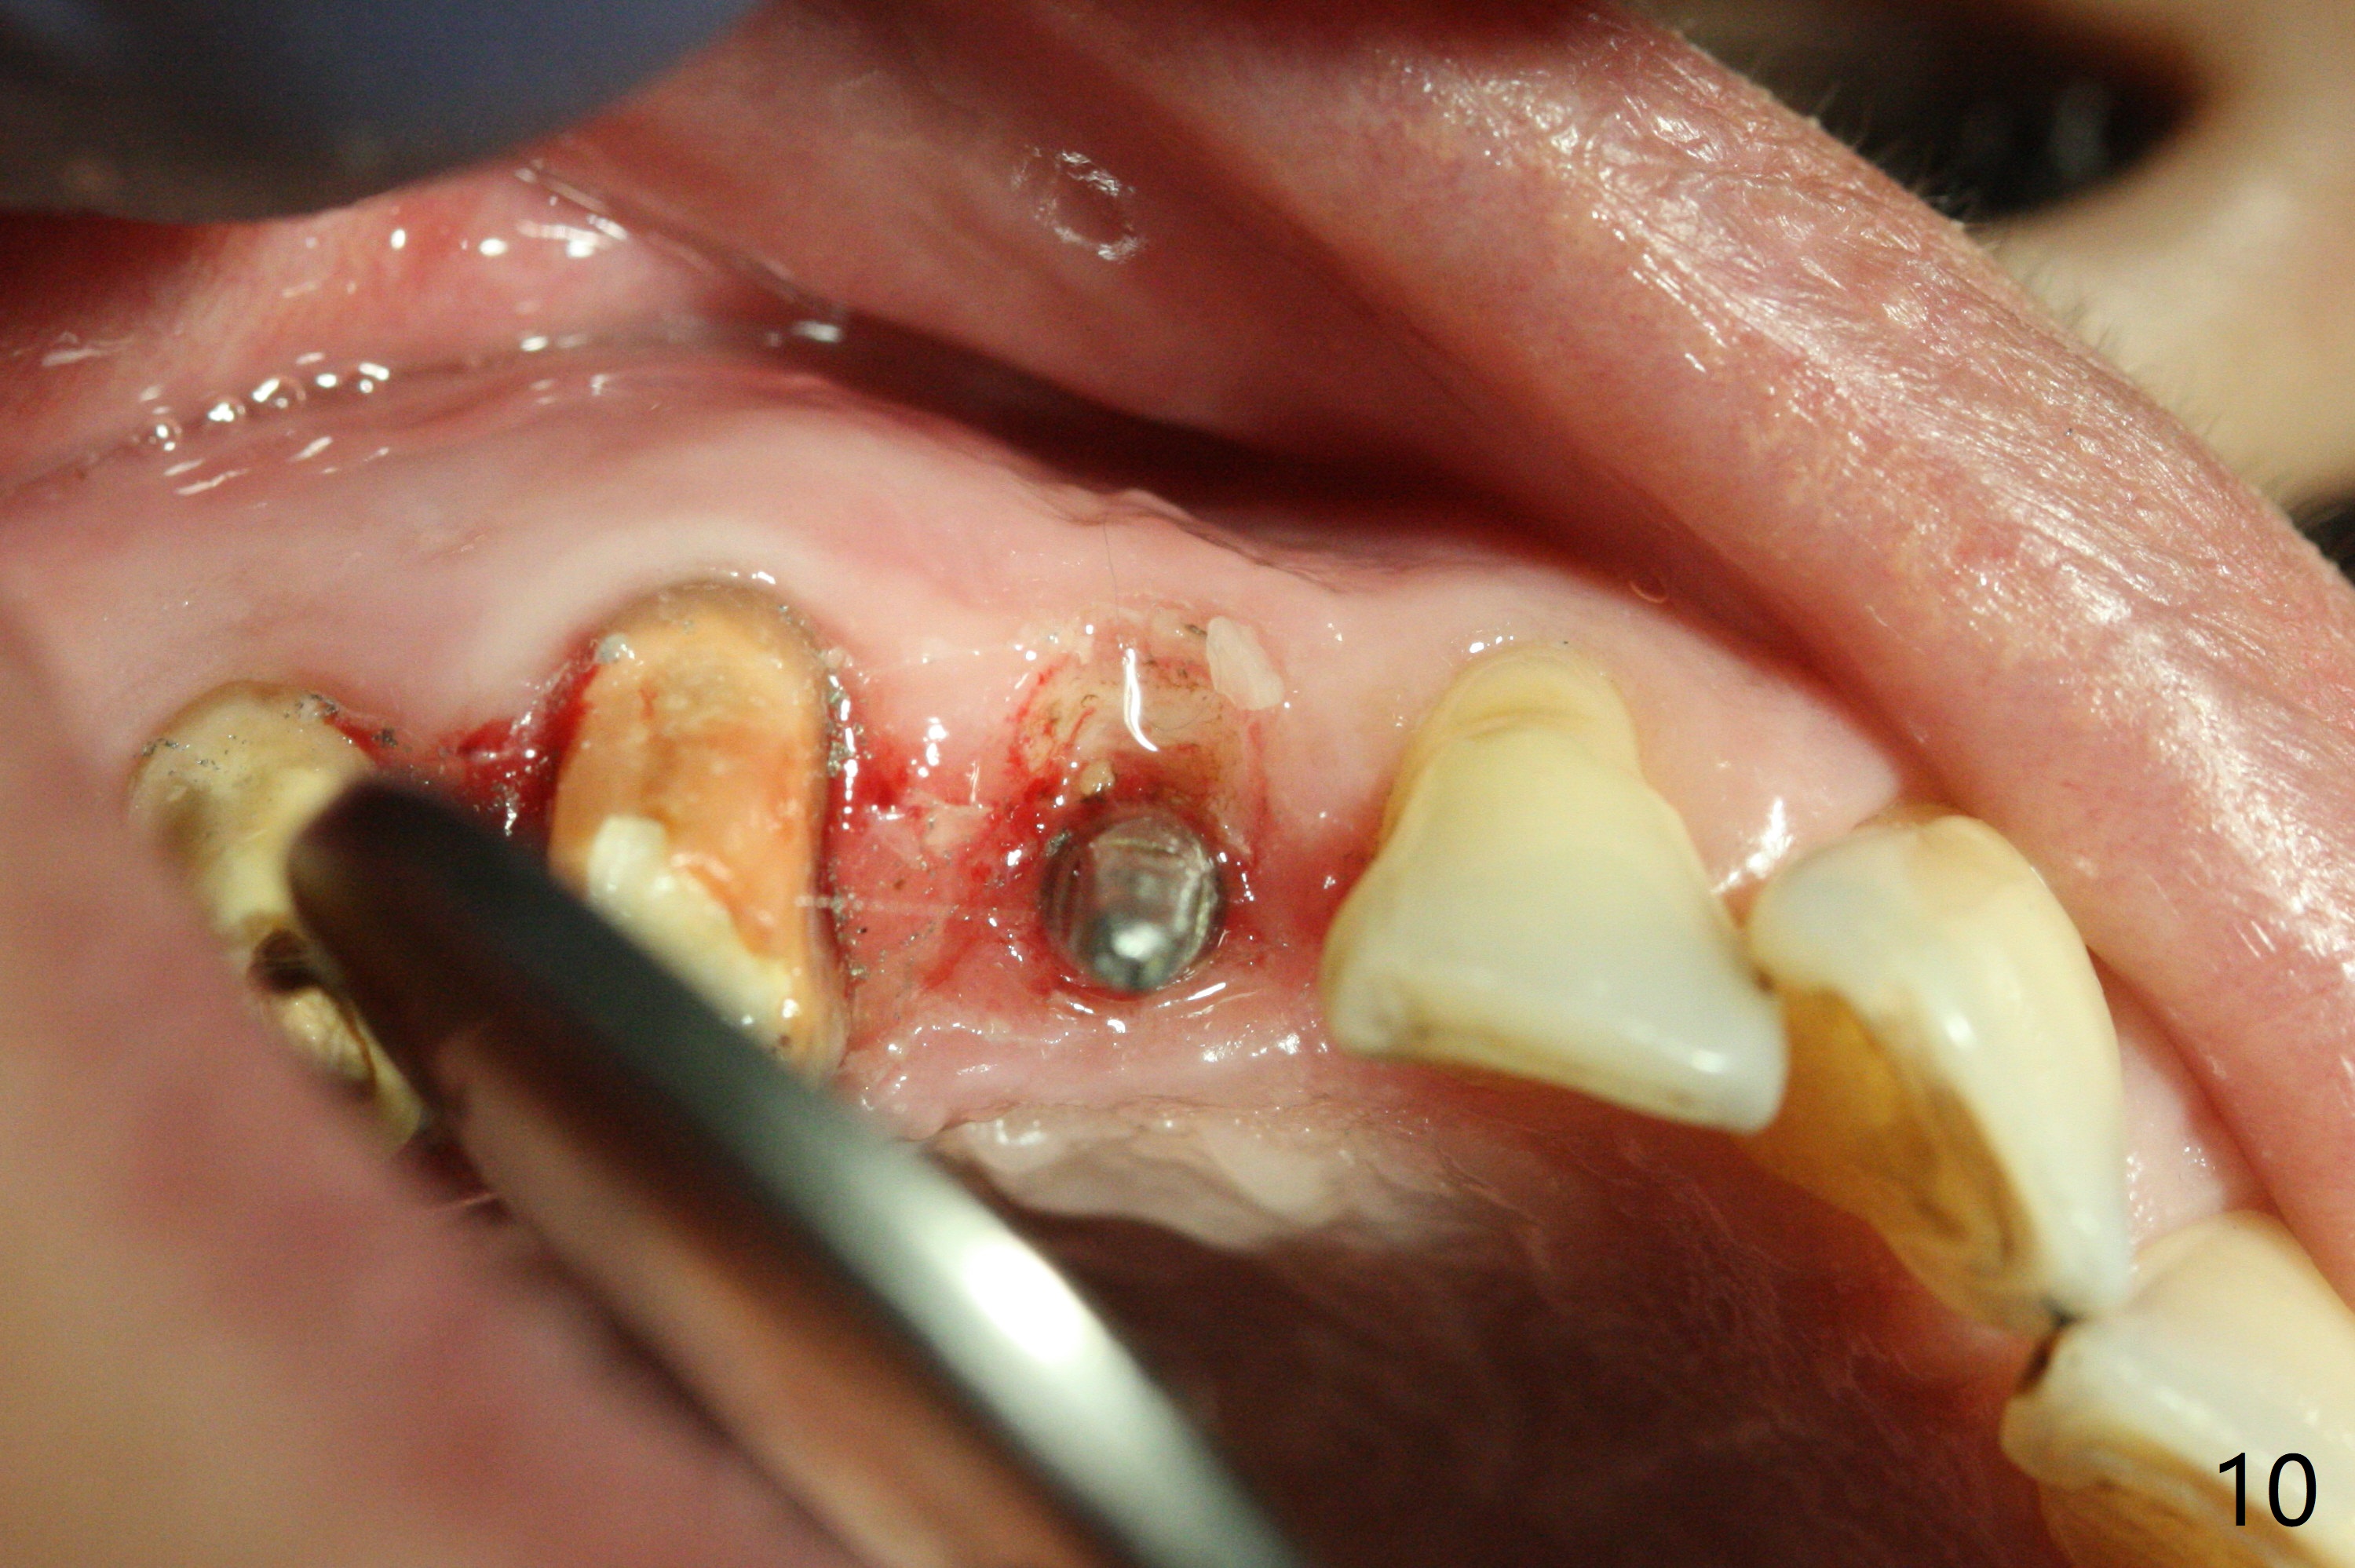

Osteotomy starts with guide and 2.2 mm drill for initial 3.5 mm palatal. A semilunar incision is made buccal to remove the impacted canine (#6 by sectioning). With direct vision buccal and palatal, the final osteotomy is finished free hand with 1.2 and 1.5 mm drills. Initially buccal perforation occurs, the osteotomy route is corrected later (Fig.1). When a 2.5x15 mm 1-piece implant is being placed, it perforates into the buccal concavity again. After redirection, the trajectory seems to be acceptable (Fig.2: CT coronal section). Three coronal implant threads are exposed partially palatal (Fig.3: CT 3-D palatal view). The implant is then turned 2-3 times with insertion torque reaching 40 Ncm. The incision is closed with suture following Osteogen plug placed in the most coronal portion of the socket (Fig.4 P) and allograft (*) in the remaining socket around the apical portion of the implant as well as palatal. The incision does not heal 1 month postop (Fig.5). PRF membrane will be placed next visit. Next visit the wound in fact is healing (Fig.6). PRF is unnecessary. The patient will return for impression 3 months postop. To be cosmetically pleasing, prepare local anesthetic and Laser for gingivectomy (Fig.7 red curved line). There is no bone loss around the implant 3.5 months postop (Fig.8). With topical, minor gingivectomy with laser creates papillae mesial and distal to the implant (Fig.9, 10 (incisal view)). After reline, there is appearance of a canine (Fig.11). The patient returns for impression 5 months postop; there is bone around the apex of the implant (Fig.12 *). The hard and soft tissues remain healthy when final restoration is delivered (Fig.13,14). The buccal plate reforms and #6 socket heals 12 months postop (6 months post cementation, Fig.15). The gingiva remains healthy at #4-6 nearly 2 years post cementation (Fig.16).